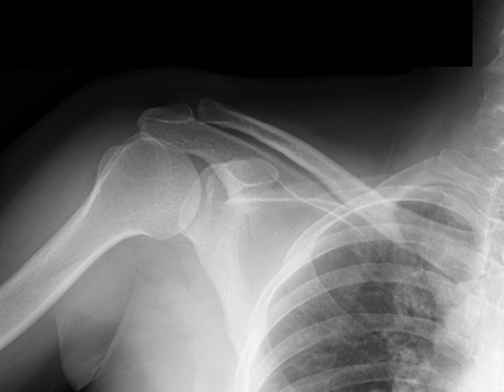

Identify the clavicle. Click the image for labeling.